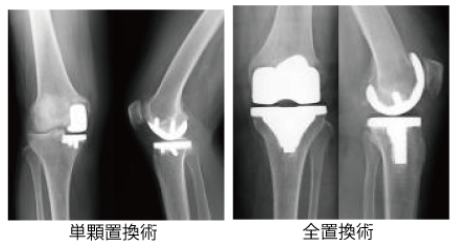

手術療法例-2 《人工関節置換術》

変形性膝関節症や関節リウマチによって傷んで変形した膝関節の表面を取り除いて、人工関節に置き換える手術です。

人工関節は、関節の滑らかな動きを再現できるようできています。手術翌日から立って歩くことができたり、入院期間も短くすむ場合が多いです。

ただし、正座がしにくくなったり、人工関節がすり減ったりゆるんだりすると入れ替えが必要となるため、定期的な検査が必要となります。